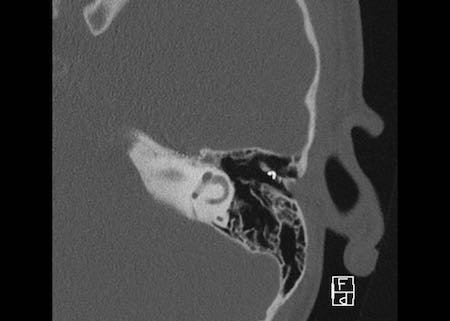

Bên trái là hình ảnh của một bé gái 2 tuổi.

Các hình ảnh từ kết quả chụp CT được thực hiện trước khi cấy ốc tai điện tử.

Quan sát thấy dị dạng nhẹ ở đỉnh ốc tai – không có sự phân tách giữa vòng thứ hai và vòng thứ ba, và trụ ốc tai xương vắng mặt.

Cống tiền đình bình thường.